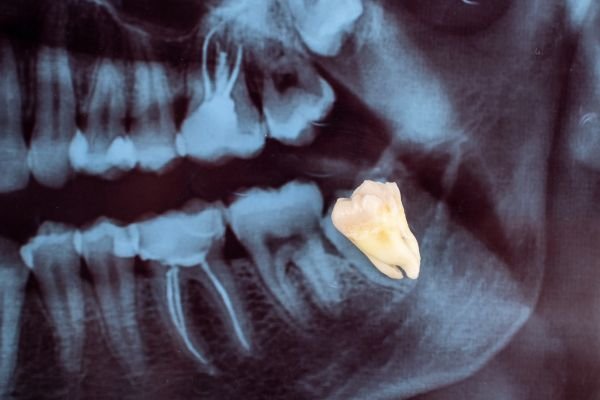

- Impaction

- A wisdom tooth can become stuck under the gums or against neighboring teeth, forcing it to grow in a tilted or crooked way.

- Abnormal Eruption Path.

Sometimes, the wisdom tooth’s natural eruption path isn’t straight, causing it to grow at an angle. This lack of room or space can result in a number of harmful effects on your overall dental health. When this occurs they are said to be impacted, indicating their inability to erupt into an alignment, which will allow them to be able to function in the chewing process.

There are several types of impactions:

Soft Tissue Impactions: There is adequate jawbone to allow the wisdom tooth to erupt but NOT enough room to allow the gum tissue to recede to allow adequate cleaning of the tooth.

Partial Bony Impactions: There is enough space to allow the Wisdom tooth to partially erupt. It cannot function in the chewing process and creates cleaning problems, among others.

Complete Bony Impactions: There is no space for the tooth to erupt. It remains totally below the jawbone or if even partially visible requires complex removal techniques.

Unusually Difficult Complete Bony Impactions: The impacted Wisdom tooth is in an unusual and difficult to remove position. This situation can also arise when the shape of the jawbone and other facial structures make removal of this tooth significantly more difficul